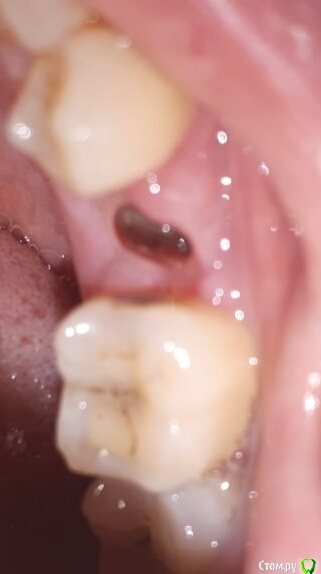

Юлия1251828 Опубликовано 2 сентября, 2019 Поделиться Опубликовано 2 сентября, 2019 (изменено) Здравствуйте. 21 августа, удалили 45 зуб, на 3 день пошла на осмотр к хирургу, десна припухла и болела, врач посмотрел, нашел кусочек еды. Сказал просто наблюдать, и промывать хлоргексидином. После этого лунка затягиваться начала, но заболел зуб рядом, ноет. Вчера, на 10 день после удаления зуба, из лунки после полоскания вышел какой то кусочек белый, как творожная масса и прожилки какие то черные. Ужасный запах. Лунка сейчас опять пустая какая то. Фото прилагаю. Сегодня только вечером поеду к врачу. Десна побаливает, и на зуб рядом надавливаю, тоже боль. Это нормально? или нет? Сегодня 11 день после удаления. Зуб кстати, очень болезненный был, было воспаление. Изменено 2 сентября, 2019 пользователем Юлия1251828 Ссылка на комментарий